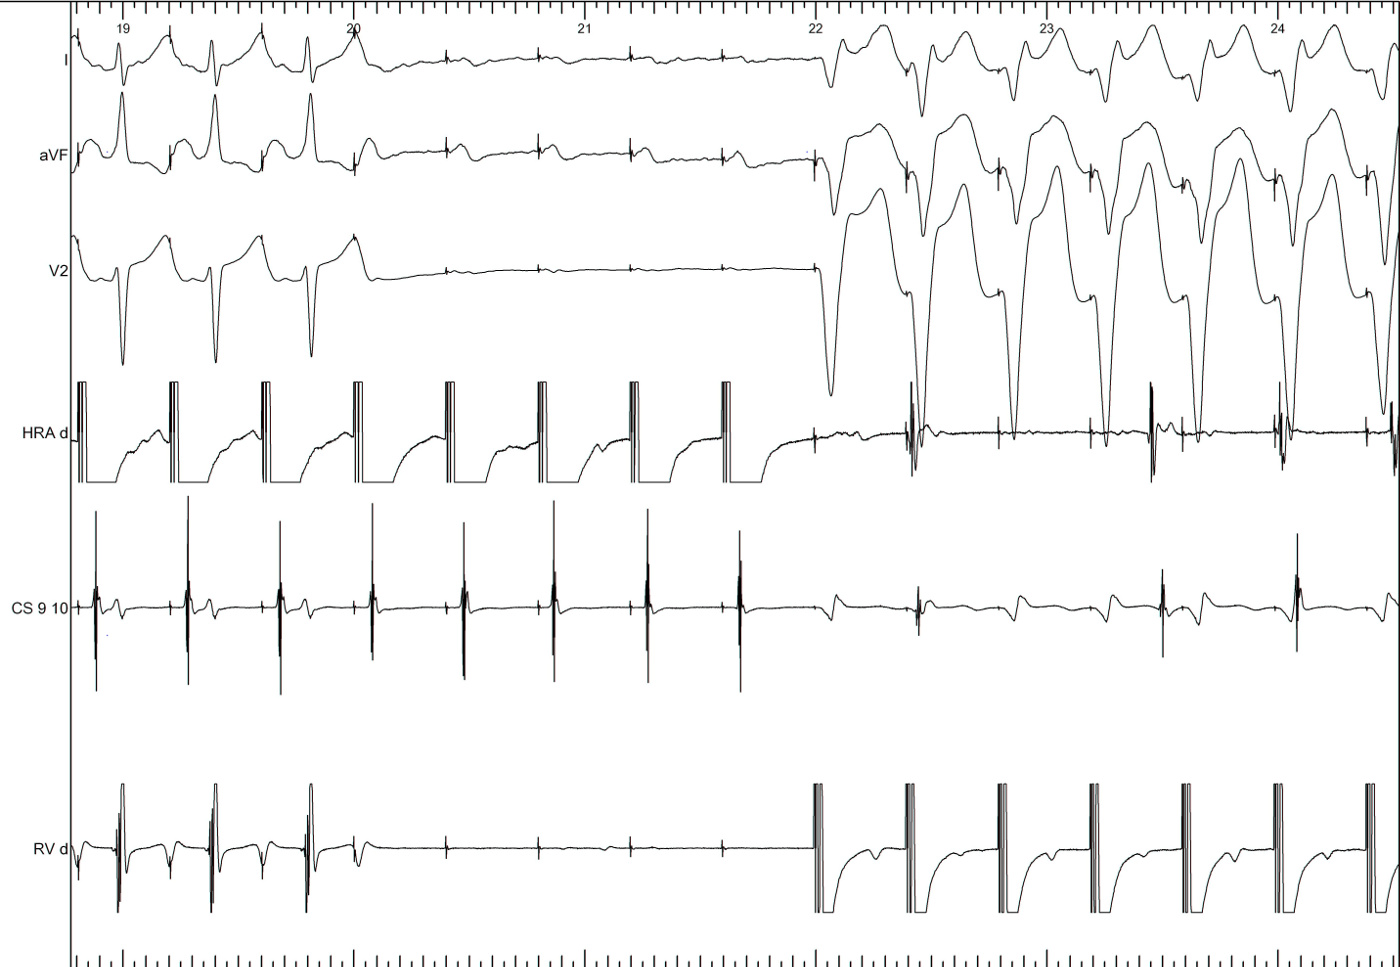

PVC during tachycardia

his_pvc.jpg

PVC terminates tachycardia

his_ref_pvc.jpg